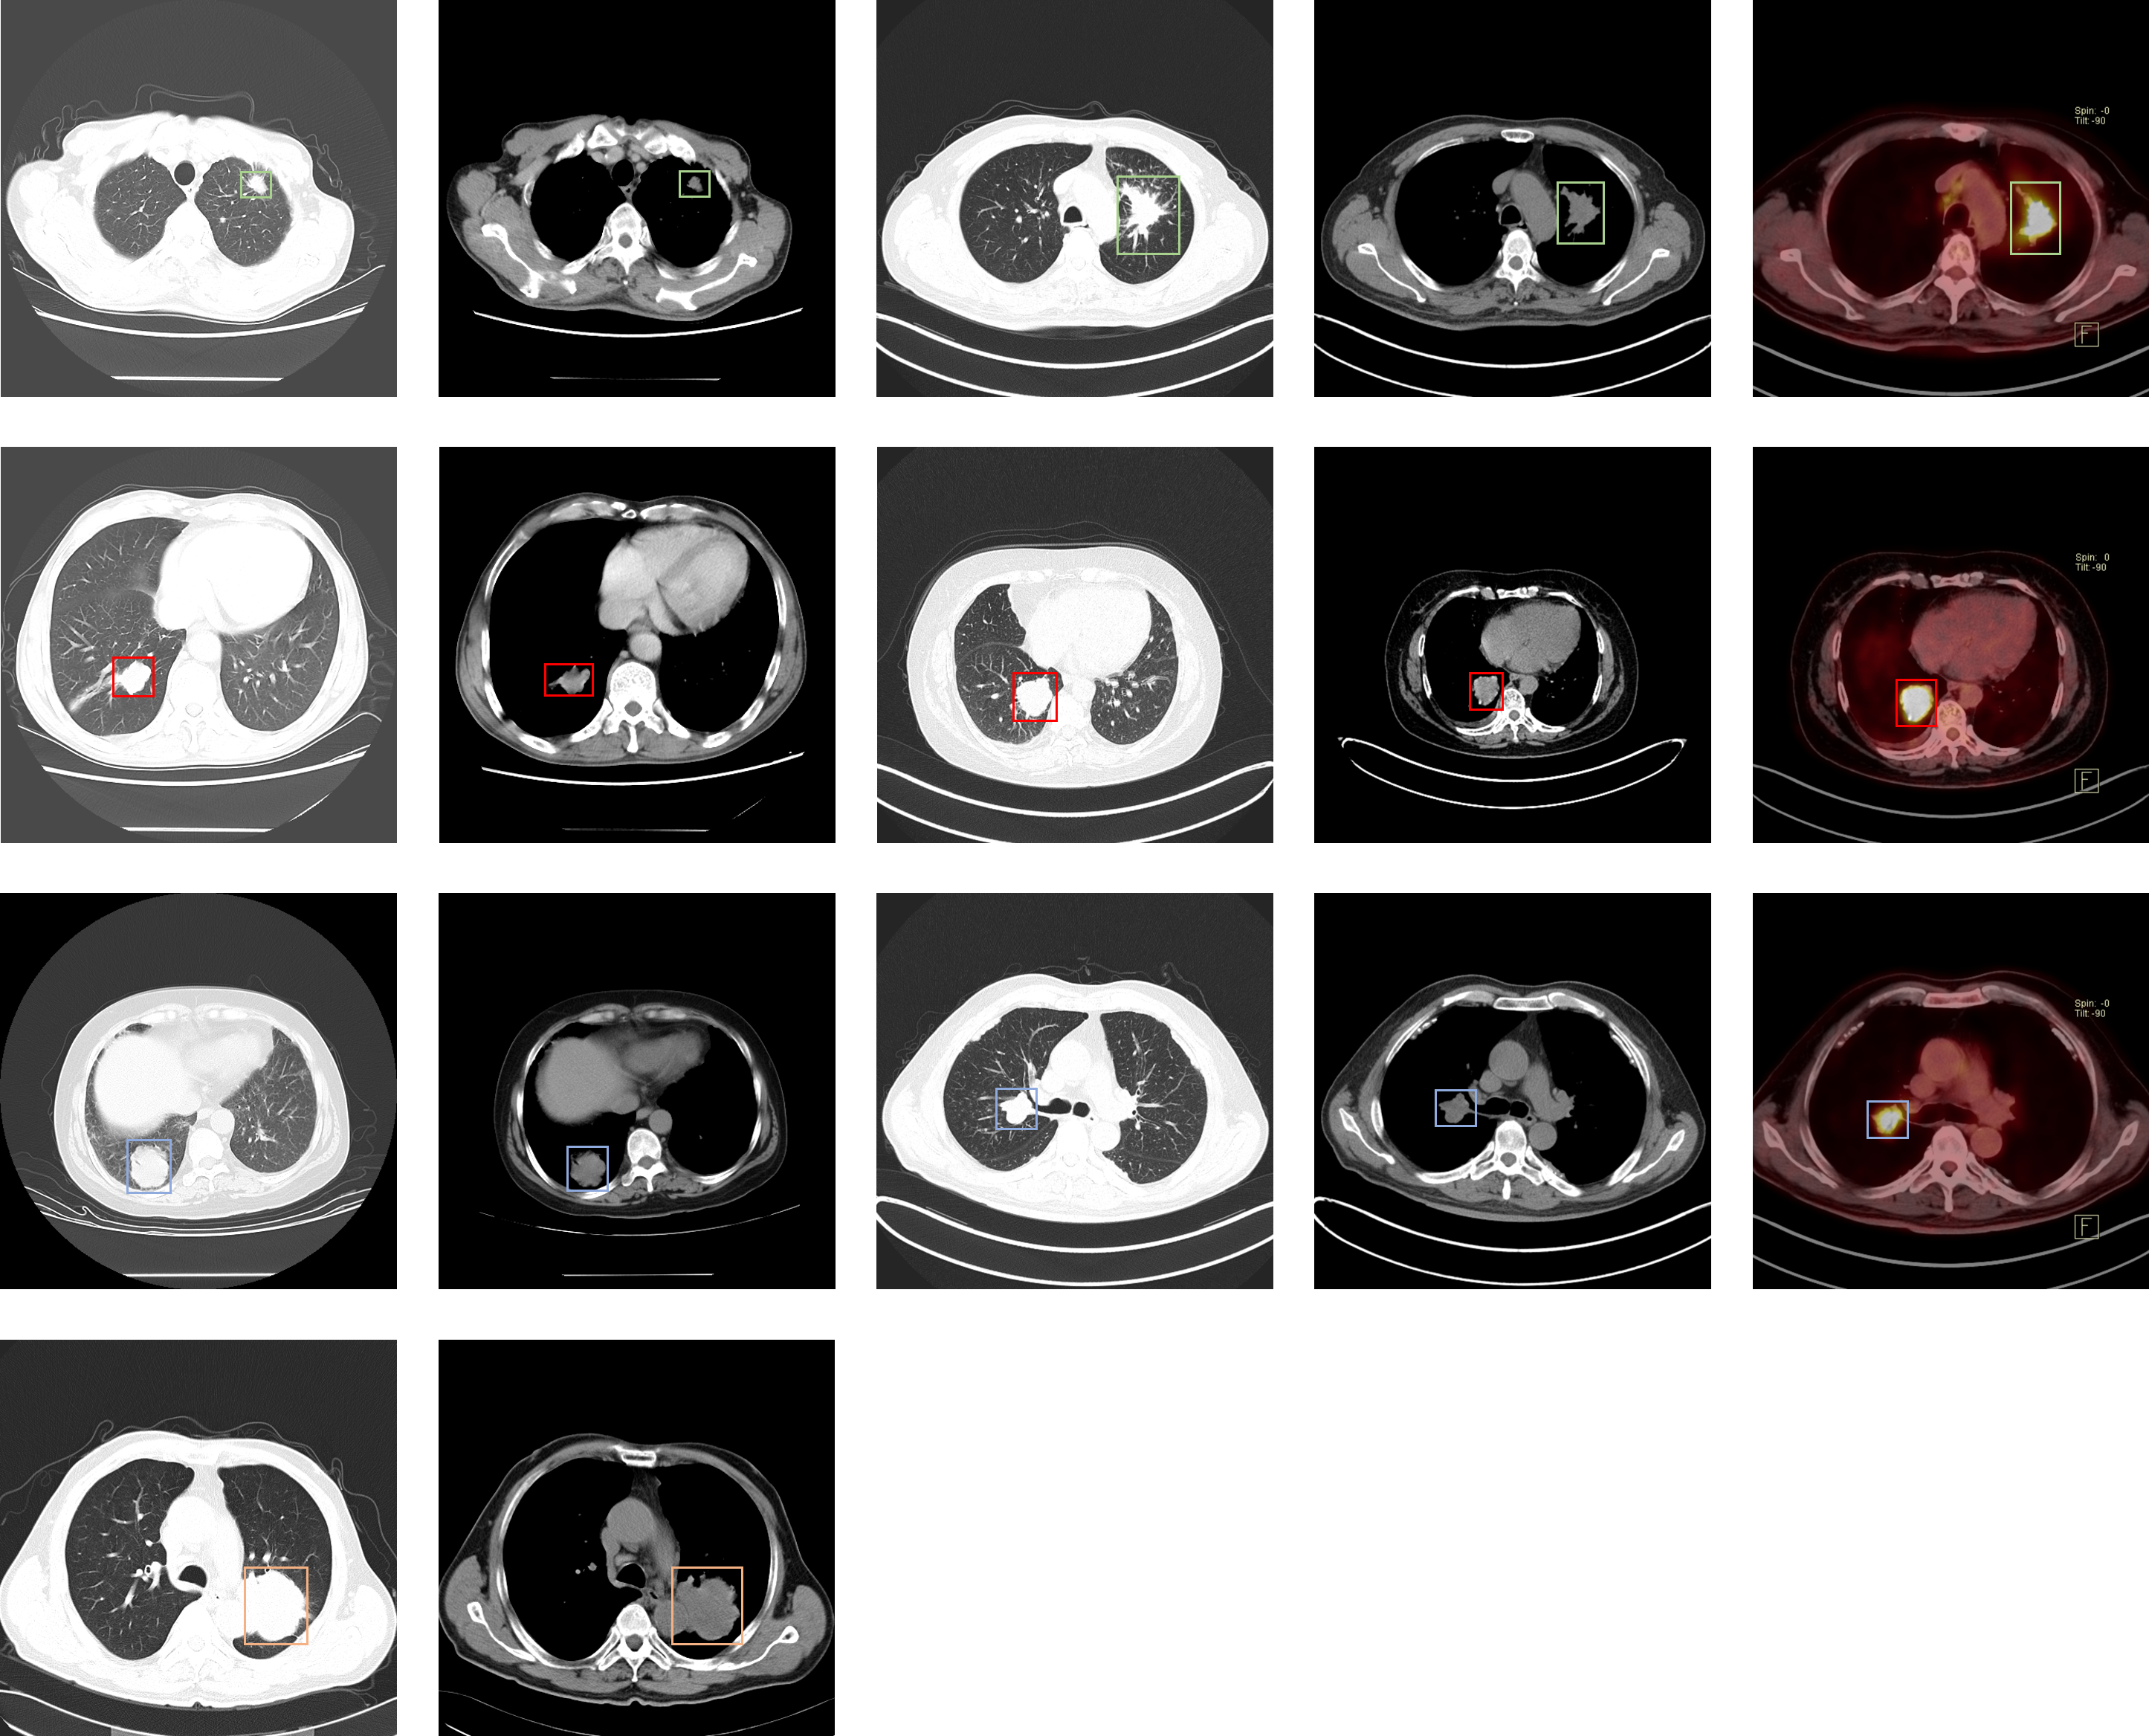

Lung-PET-CT-Dx

| Lung-PET-CT-Dx | 肺癌 | 目标检测 | CT | 363 | xml | dcm |